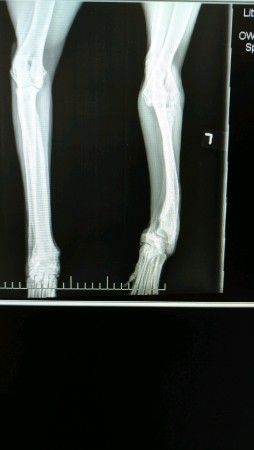

Earl struggles to run and play because he has a bowed front leg!

Earl has had his wellness check, shots, and his neuter surgery. But he has a bowed left front leg and struggles to run and play like a normal puppy. We believe that Earl's leg may have been injured when he was tiny puppy, and it was not set when it could have been. He has had x-rays that have determined that his growth plates are closed. Earl is ready for his next journey... to enjoy life and play with his buddies.

AGR explored many options to fix Earl's leg with a veterinarian and an orthopedic surgeon. All of them are expensive, but we want Earl to have a normal life. Amputating Earl's leg is much too drastic... we feel that would leave Earl without further choices. AGR has decided to work with Kate Titus, Owner of A Loyal Companion who is manufacturing a brace and orthotic for Earl. This will give Earl the ability to move, run, and play like the Greyhound he was meant to be!

Growth plate X-rays and office visit for fitting of brace –

Little Critters Vet Hospital, Gilbert: $200